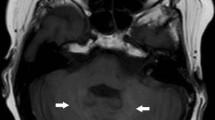

The use of linear extracellular GBCA led to visible changes in SI ratios and measurable Gd depositions in the rat and dog brains [15,16,17,18]. Most depositions were in perivascular foci in the DN and GP [15], with evidence of co-localisation to parenchymal iron [18]. The amount of deposition in rat brains occurred independent of age or sex [17]. Local blood-brain barrier disruptions did not lead to an increase in T1 SI ratios or Gd deposition [19]. Active inflammation showed higher Gd concentration in inflamed areas in mouse brains [20], while the presence of diabetes led to lower brain concentrations [21]. There was a decreased concentration over time in all brain regions, but long-term retention over 1 year occurred preferentially in the rat DN [16]. Despite DN and GP being the brain structures mostly involved by Gd deposition (Figure 1), it should be mentioned that Gd was also suggested to be deposited in other brain areas including pulvinar thalami, pons, frontal lobe cortex and white matter, and cerebellar cortex and white matter, mainly at the level of capillary endothelium and neural interstitium [18, 22, 23]. In addition, increased T1 signal intensity of the anterior pituitary gland, notably not lined by blood–brain barrier, has also been reported after serial exposure to extracellular linear GBCA (Figure 2) [24, 25].

Slightly greater T1 signal intensity of the anterior pituitary gland in sagittal T1W image acquired at post-injection time delay of 1 day and only 1 previous GBCA exposure (arrow in A) with respect to a similar image acquired at post-injection time delay of 180 days and four previous GBCA injections (arrow in B). The lower panel shows the decreasing trend of normalised ratios from minimum to maximum post-injection time delay of each individual patient.